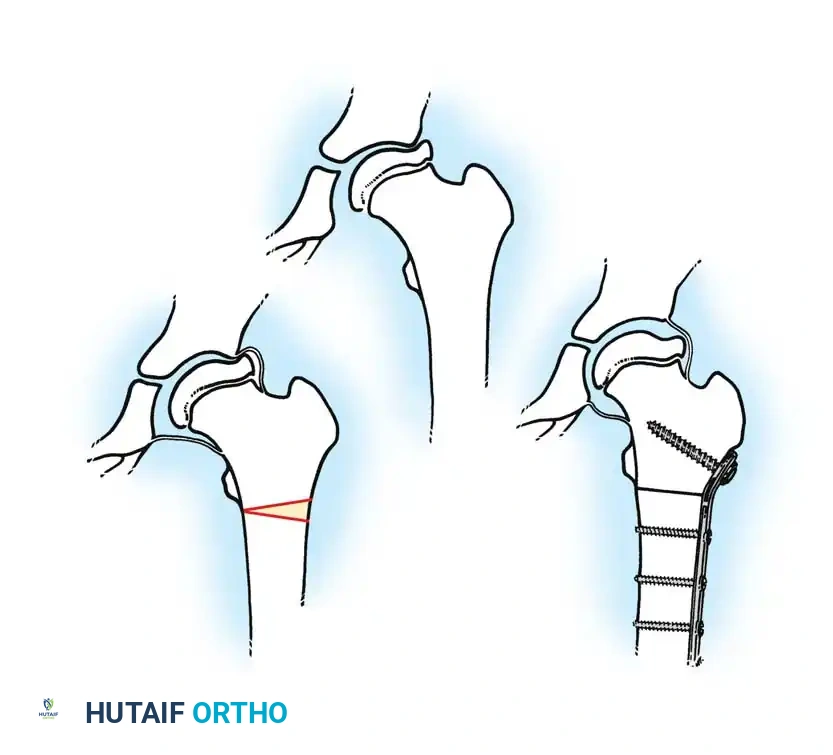

Surgical Management: Femoral Varus Derotational Osteotomy (VDRO)

Surgical containment is indicated for children over the age of 8 with Herring Group B or B/C disease, or any child exhibiting progressive loss of containment and "head-at-risk" signs.

The Femoral Varus Derotational Osteotomy (VDRO) is a powerful technique that redirects the vulnerable anterolateral portion of the femoral head deeply into the acetabulum, relieving it from the deforming forces of the acetabular rim.

Step-by-Step Surgical Technique:

1. Positioning: The patient is placed supine on a radiolucent Jackson table. A bump is placed under the ipsilateral hip.

2. Approach: A standard lateral approach to the proximal femur is utilized. The fascia lata is incised, and the vastus lateralis is elevated off the intermuscular septum and reflected anteriorly to expose the proximal femoral shaft.

3. Guidewire Placement: Under strict fluoroscopic guidance, a guidewire is advanced into the femoral neck and head, parallel to the planned angle of the blade plate. The goal is typically to achieve a neck-shaft angle of 110 to 115 degrees.

4. Osteotomy: A transverse or closing-wedge osteotomy is performed at the intertrochanteric level using an oscillating saw.

5. Derotation and Varus: The distal fragment is externally rotated (typically 15-20 degrees) to correct the anteversion, and the proximal fragment is allowed to fall into varus.

6. Fixation: A pediatric locking plate or a fixed-angle blade plate is impacted into the proximal fragment and secured to the distal shaft with cortical screws. Compression is applied across the osteotomy site.

Postoperatively, the varus angulation results in a temporary limb length discrepancy and a Trendelenburg gait, which typically resolves as the child grows and the neck-shaft angle remodels.